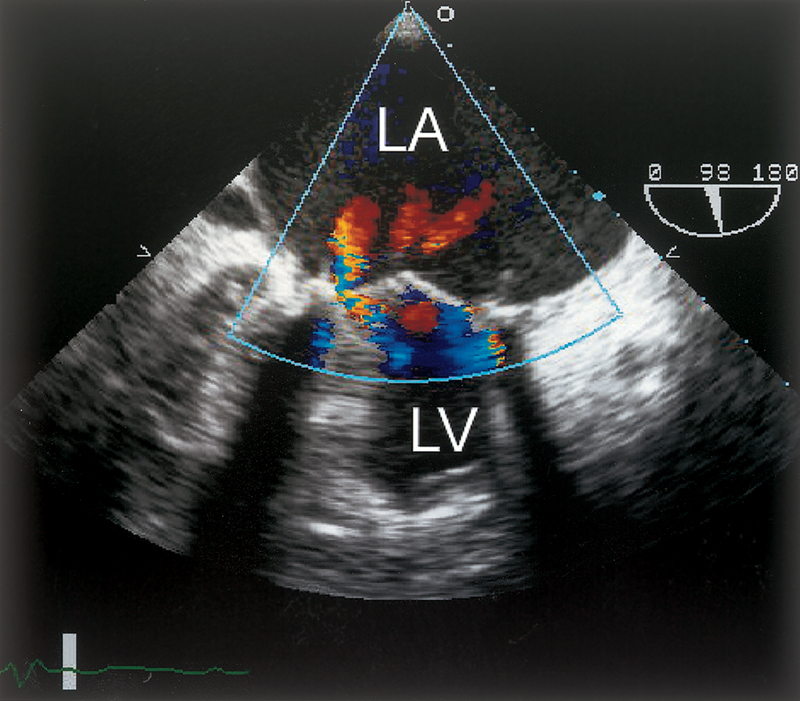

فحوصات تشخيصية لبعض امراض القلب والشرايين التاجية